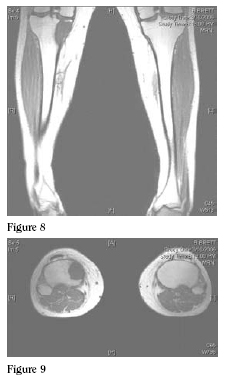

MRI showed the mass to involve the medial portion of the proximal

tibial metaphysis and epiphysis. Staging studies, including

computed tomography

scanning of the chest and

whole body bone scan,

were done which did not

show any evidence of

metastatic disease to the

lungs or other bony sites.

The patient was referred

to medical oncology for

induction of chemotherapy

for osteosarcoma. The

patient underwent three

months of neo-adjuvant

chemotherapy and then

underwent complete restaging

examinations followed

by operative resection

for local control of the

tumor. (Figures 8 and 9)